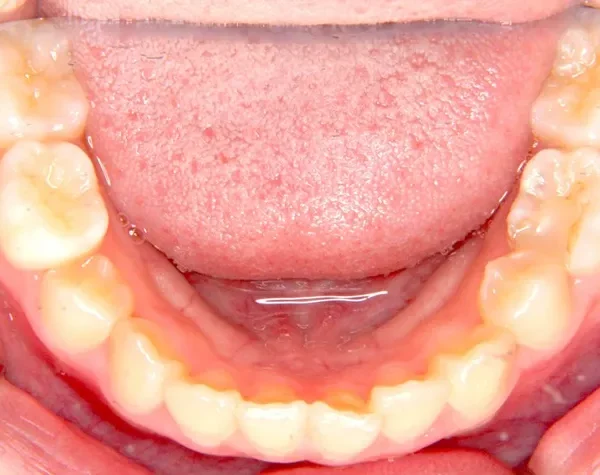

• 初診

上下がガタガタで犬歯の生えるすきまがありません。

このままだと犬歯の生えるスペースがありません。放っておくと犬歯が上の位置からはえ、牙のようになってしまいます。